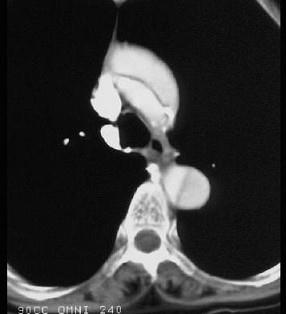

问题 男,64岁,突感胸部剧痛2h,呈撕裂样,并向背部放射,有高血压病史10年,含服硝酸甘油3片不能缓解,CT检查如图所示。首先应考虑的诊断是 ( )

选项 A、急性胸膜炎 B、急性心肌梗死 C、急性胆囊炎 D、急性胰腺炎 E、主动脉夹层

答案 E